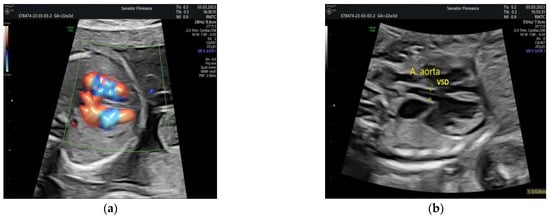

| Gestational age at cardiologic diagnosis | 22 weeks |

| Cardiologic diagnosis | IAA type B, malalignment-type VSD, pulmonary valve dyplasia, ARSA |

| Postnatal echocardiography | Prenatal diagnosis confirmed |